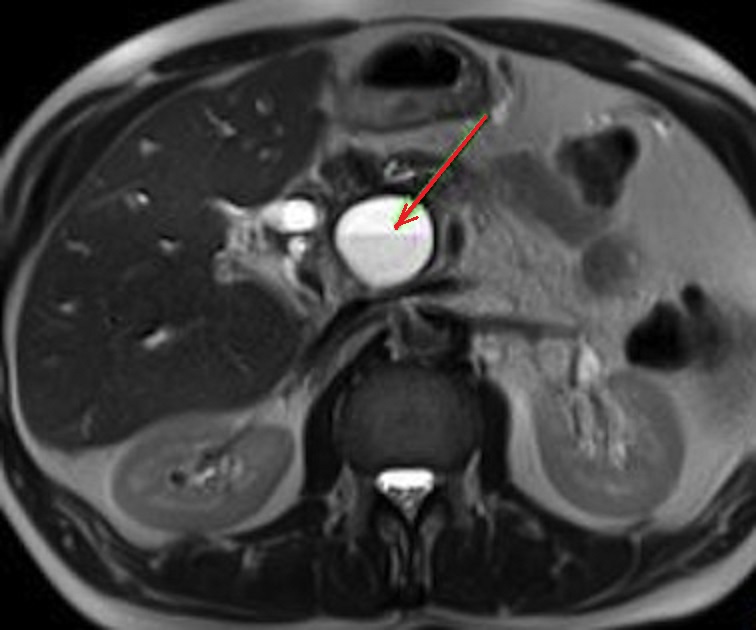

Meme cas en coupe IRM axiale

a ponderation T2 . Aspect radiologique lesionaire

est une kyste arrondie liquidienne de tres

hypersignal a bord lisse , regulier situe a la tete

du pancreas . Image IRM coupe axiale a ponderation

sur T2 |